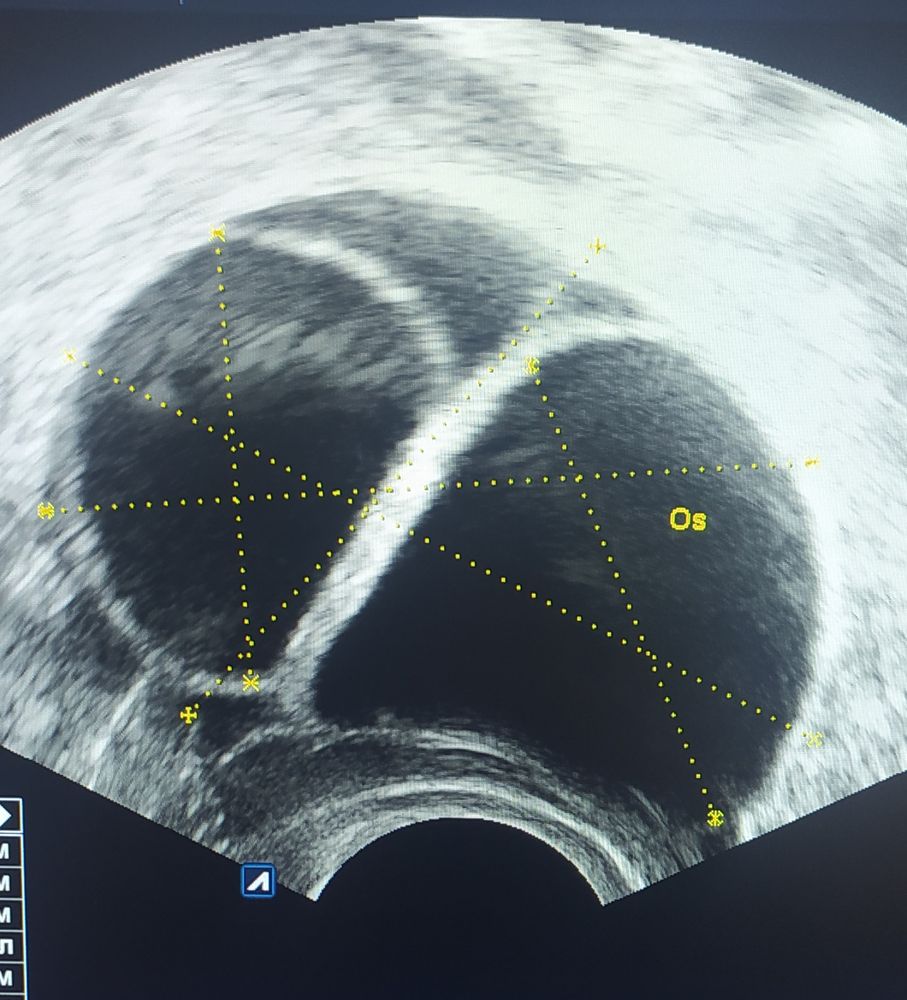

Овуляция( тесты на овуляцию)Фолликулярная киста или киста ЖТ? Размеры 32 и 31 мм.

Мира, я пишу про кисту ЖТ. В интернете фото глянула, вроде похоже, а вроде и нет...

у меня просто тоже были такие,то есть одна два месяца подряд образовывалась и я интересовалась,она именно как шарик который не лопнул...как у вас,а киста жт это скуолупка от того самого фоллика и она со рваненькими краями,она не может иметь четких ровных контуров...но наш организм загадка

Не ЖТ к сожалению. Посмотри в интернете снимки ЖТ. Контуры другие.

Poppiholla,

Да, похоже не лопнули.... Почему блин? Аж зло берёт 😠 в чем проблема блин? Своей О нет, а при стимуляции по всем правилам кисты получаются! Что за ерунда...😭 Во вторник опять на УЗИ пойду. Эндометрий 14,3 мм